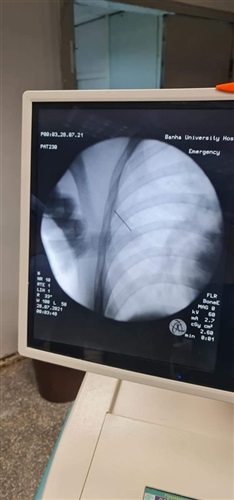

نجح الاطباء بمستشفى بنها الجامعى، فى استخراج "دبوس تنجيد"، صوبه منجد فى صدر زميله بالخطأ، عن طريق دباسة التنجيد ذات ضغط الهواء العالى، مما أدي إلي انطلاق الدبوس مثل الرصاصة واختراق صدر الشاب العشريني.

وأوضح الدكتور محمد الجزار استشارى جراحة القلب والصدر ، أن الدبوس استقر بعضلات الصدر، واخترق جزء منه القفص الصدري، مما أدي إلي استرواح هوائى وتجمع دموي بالغشاء البللورى المبطن للرئة اليمنى، وعلى الفور تم إدخاله لغرفة العمليات علي الفور بطوارئ المستشفى، وجري استخراج الدبوس باستخدام جهاز الأشعة (c-arm).